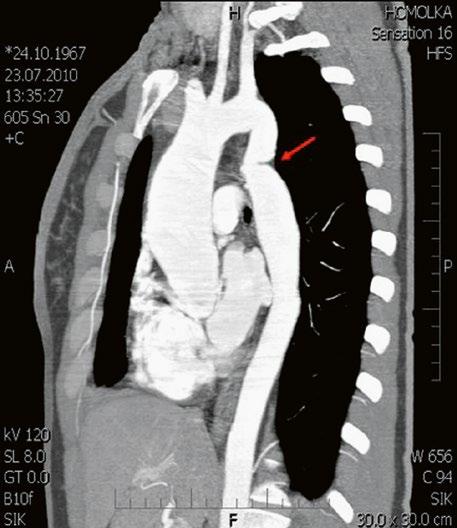

Supravalvární pulmonální stenóza a stenózy větví plicnice bývají součástí komplexních VSV (např. Fallotovy tetralogie) nebo syndromů (Williamsův syndrom, syndrom Noonanové, syndrom vrozené rubeoly, Alagillův syndrom aj.) (Obr. 45.39). Získané stenózy větví plicnice, ale i úplný uzávěr větve plicnice můžeme vidět po spojkových operacích podle BlalockaTaussigové (Obr. 45.40, Obr. 45.41). Pro zobrazení supravalvárních a periferních stenóz plicnice je optimální CT angiografie (Obr. 45.40, Obr. 45.41, Obr. 45.42, Obr. 45.43).

Obr. 45.40 CT angiografie, 8mm stenóza a deformace levé větve plicnice (šipka) po spojkové operaci podle BlalockaTaussigové v dětství LPA – levá větev plicnice, PA – kmen plicnice, RPA – pravá větev plicnice

Obr. 45.41 Uzávěr levé větve plicnice jako následek provedené spojky podle BlalockaTaussigové v dětství, CT angiografie